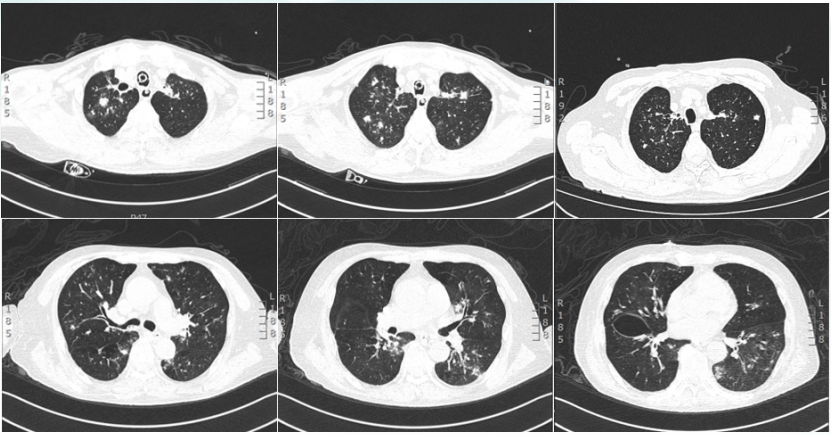

5月25日,患者仍感气促,血气分析(鼻导管吸氧5 L/min)pH 7.29PaCO2 88 mmHgPaO2 53 mmHgSaO2 83 %HCO3- 42.3 mmol/L,再次转入RICU。复查胸部CT:病灶部分较前吸收变小,但空洞内部变实,另有新增空洞及结节(图6)考虑除了基础疾病,感染也未得到很好的控制。

图片

6  复查胸部CT(2023-05-25)